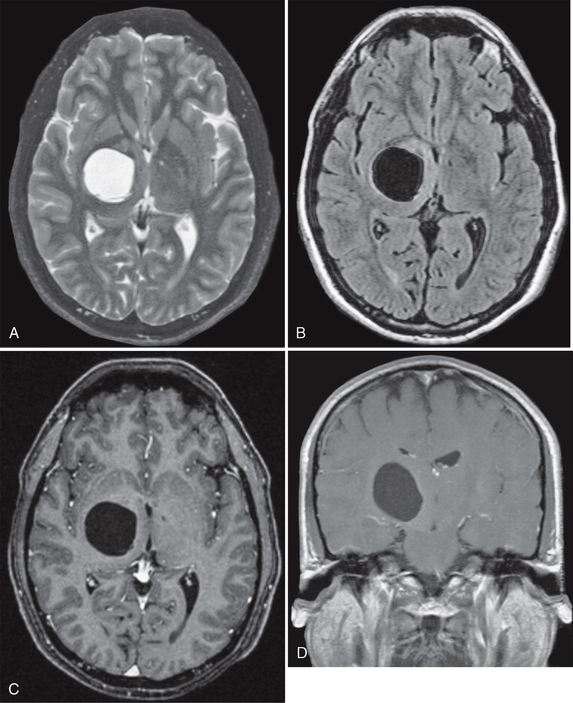

Іноді на МРТ можна побачити сліди так званих «тихих» або мікроінсультів — маленьких ділянок пошкодження через порушення кровотоку. Людина могла навіть не відчути симптомів, але такі зміни свідчать про проблеми з судинами та загалом підвищують ризик великого інсульту в майбутньому. У такому випадку лікар зазвичай рекомендує додаткове обстеження та контроль факторів ризику. - Кісти головного мозку.

Кіста — це порожнина, заповнена рідиною. На МРТ вона виглядає як чітко окреслена ділянка. Більшість кіст є вродженими або випадковою знахідкою. Як правило, вони не становлять небезпеки і не потребують лікування, якщо не збільшуються і не викликають симптомів. Лише в окремих ситуаціях потрібне спостереження або втручання.